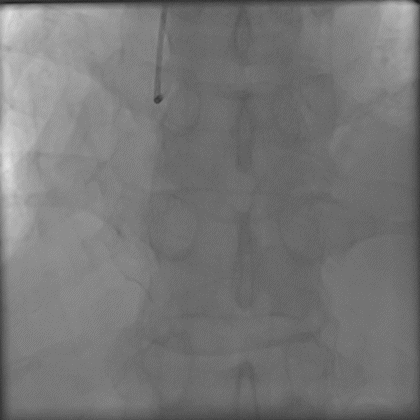

3.0后扩球囊Base;

P200短距离前行后再也不能前行,

Gaia3磨进2段,进入内膜下,前进艰难;